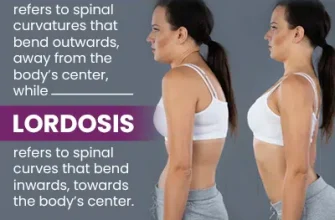

Kyphoscoliosis is a spinal deformity characterized